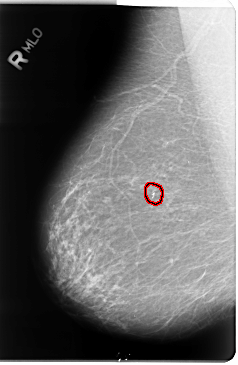

B_3049_1.RIGHT_MLO

FILE: B_3049_1.RIGHT_MLO.OVERLAY

TOTAL_ABNORMALITIES 1

ABNORMALITY 1

LESION_TYPE CALCIFICATION TYPE PLEOMORPHIC DISTRIBUTION CLUSTERED

ASSESSMENT 4

SUBTLETY 4

PATHOLOGY BENIGN

TOTAL_OUTLINES 1

BOUNDARY